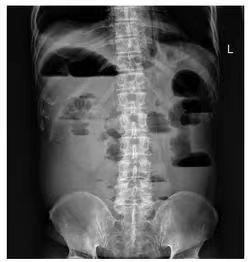

肠梗阻,简单讲是指肠道的正常运动受到阻碍,导致食物、液体和气体无法顺利通过肠道。

急性肠梗阻最常见的原因包括肠粘连、肿瘤和疝气。腹部手术病史引起的粘连是小肠梗阻的主要原因,占病例的60%至75%。继发于肿瘤的梗阻在大肠中更常见。其他原因包括炎症性肠病、肠套叠、肠扭转、胆结石和肠管异物。